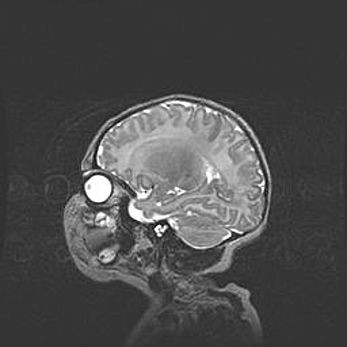

Мальформация Денди-Уокера. Киста задней черепной ямки.

Агенезия мозолистого тела.

Возраст: 2,5 месяца

Вес: 2420 г

Пол: женский

Окружность головы: 37 см

Срок гестации: 32 недели

Мальформация Денди—Уокера — редкий вид патологии ЦНС, представляющий собой врожденный порок развития каудального отдела ствола и червя мозжечка, ведущий к неполному раскрытию срединной (Мажанди) и латеральных (Лушка) апертур IV желудочка мозга. Для этогно синдрома характерна триада симптомов: гипотрофия червя мозжечка и/или полушарий мозжечка, кисты задней черепной ямки, гидроцефалия различной степени. В 70% случаев порок сочетается и с другими аномалиями головного мозга, в частности с агенезией мозолистого тела.